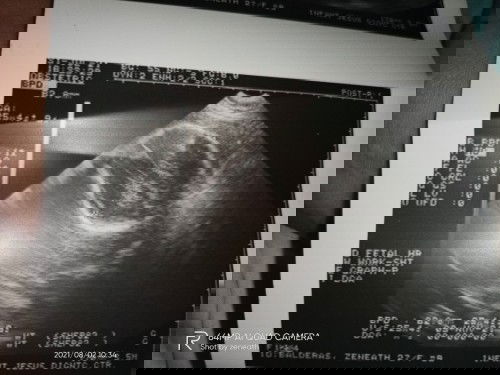

not sure mommy . kahit aq diko alam pano tinitignan π π π